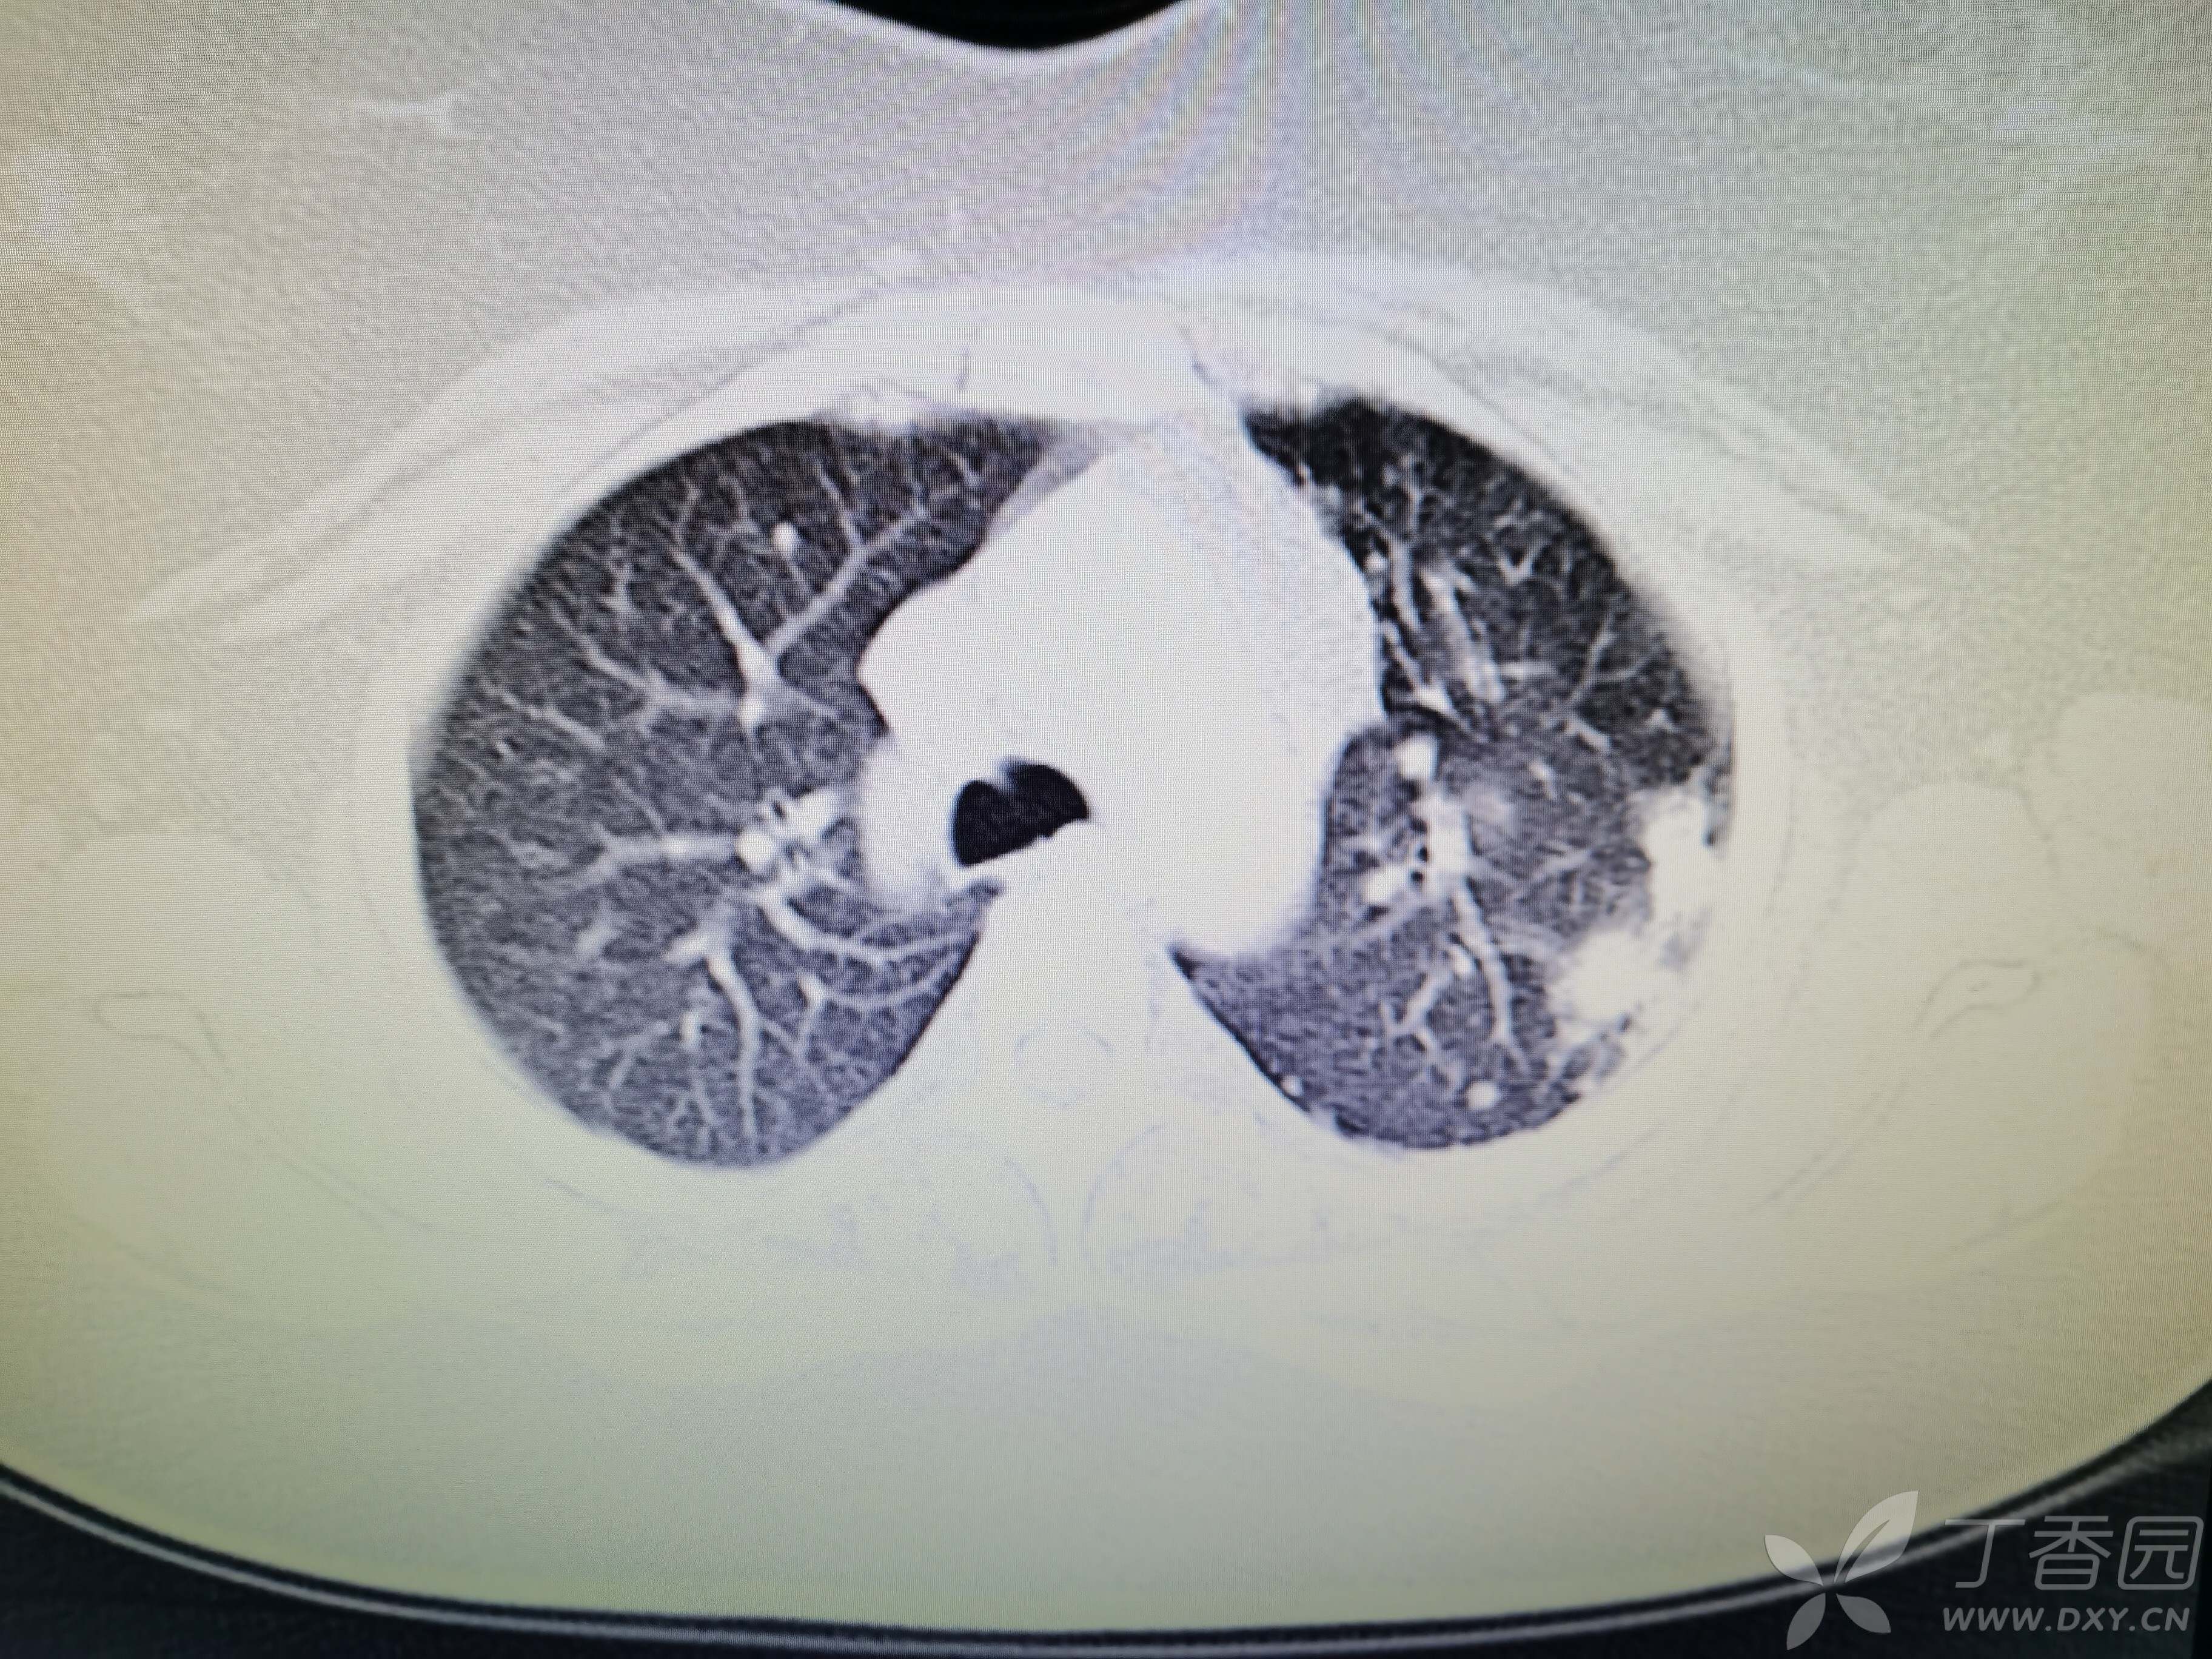

基本信息:女,三十几岁,印度人。。

胸部CT:

如题:猜肺部病灶病理。。